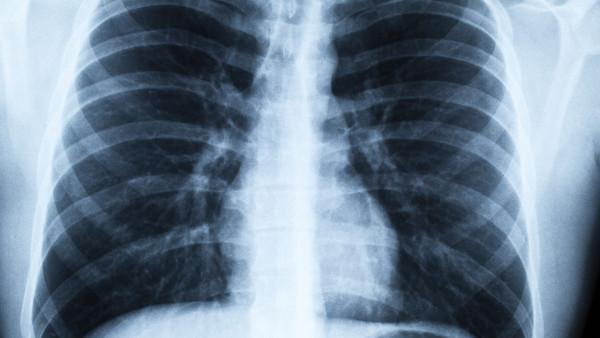

间质性肺病(Interstitial Lung Disease, ILD)是一组包括多种疾病的系列,它们对肺部间质(肺泡和血管之间的支持组织)造成损害和炎症。这些疾病可能导致肺部纤维化,使呼吸困难,并最终可能导致氧气摄取和二氧化碳排出受影响。因此,对于患有间质性肺病的患者来说,及时的疾病管理至关重要。 早期诊断和治疗的重要性 早期诊断对于间质性肺病的有效管理至关重要。一旦症状出现,患者应尽快就医,接受专业医生的诊断和治疗。常见的间质性肺病包括特发性肺纤维化、间质性肺炎等,每种疾病都需要个体化的治疗方案。 确定导致因素 在制定治疗方案时,医生需要确定导致患者间质性肺病的确切原因。有些情况下,可能是由于环境因素(如吸入有害颗粒物)、特定职业暴露、自身免疫性疾病等引起。针对不同原因导致的间质性肺病,治疗方案可能会有所不同。 个体化治疗方案 一旦确诊,医生会制定个体化的治疗方案,以帮助患者管理疾病并减轻症状。治疗方案可能包括药物治疗、氧疗、康复和其他支持性治疗。特发性肺纤维化等慢性间质性肺病通常需要长期治疗,包括对症状的缓解和病情的控制。 营养和运动 良好的营养和适当的运动对于间质性肺病患者同样至关重要。均衡饮食可以增强患者的免疫系统,提高身体对疾病的抵抗力。适度的运动可以增强肺部功能和整体健康。 定期随访 定期随访对于间质性肺病患者的疾病管理也非常重要。医生可以通过定期检查评估疾病的进展情况,调整治疗方案,以确保患者的病情得到有效控制。 结语 综上所述,间质性肺病是一组临床复杂的疾病,需要综合治疗和持续的管理。通过早期诊断、个体化治疗方案、健康的生活方式和定期随访,间质性肺病患者可以有效管理病情,提高生活质量,延长寿命。因此,患者和医护人员都应该共同努力,以应对这一挑战性的疾病。

社区获得性细菌性肺炎的慢性并发症

社区获得性细菌性肺炎(CAP)是一种常见的感染疾病,通常由各种细菌引起,影响社区中的个人。大多数CAP病例通过抗生素治疗可以得到有效控制和治愈,但有时CAP可能会引发慢性并发症,给患者带来更多的健康挑战。 CAP的慢性并发症包括但不限于肺部疤痕形成、慢性支气管炎、肺气肿和肺囊肿等。这些并发症可能会导致患者长期的肺部功能受损,影响其生活质量并增加患者因呼吸系统问题而需要就医的次数。 首先,肺部疤痕形成是CAP患者常见的慢性并发症之一。疤痕组织的形成可能会导致肺部组织的硬化和变形,从而影响呼吸功能。患者可能会感到气短和呼吸困难,甚至在严重的情况下需要接受呼吸治疗。 其次,慢性支气管炎是另一个常见的CAP并发症。这种情况下,支气管可能会受到炎症的长期影响,导致支气管通畅性降低,并且容易引发反复的感染,增加患者患上肺部疾病的风险。 肺气肿和肺囊肿也是CAP患者可能面临的慢性并发症。肺气肿指的是肺部组织的气腔过度扩张,导致肺功能下降,气短和呼吸困难的症状可能会持续存在。而肺囊肿则是肺部组织内的小囊肿或液泡,如果囊肿破裂或感染,可能会引发更严重的并发症。 要预防CAP慢性并发症的发生,及时诊断和治疗CAP至关重要。任何出现CAP症状的个体应尽早就医,接受医生的建议并完成治疗方案。此外,定期的肺部检查和保持健康的生活方式也有助于降低慢性并发症的风险。 总而言之,CAP的慢性并发症可能会给患者带来持久的健康问题,影响其日常生活和工作。因此,对于CAP患者来说,重视疾病的早期诊断和治疗,以及持续的随访和管理至关重要,以减少慢性并发症的发生和发展,从而维护良好的生活质量。